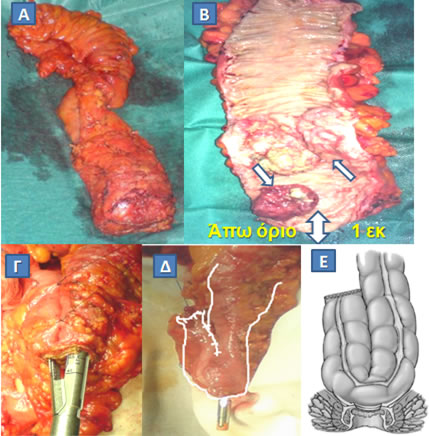

Τα καρκινώματα του κατώτερου τριτημορίου παραδοσιακά αντιμετωπίζονταν με κοιλιοπερινεϊκή εκτομή, αλλά, με την καθιέρωση του ασφαλούς ογκολογικού άπω ορίου στο 1 εκατοστό, η εκτέλεση μιας «πολύ» χαμηλής πρόσθιας εκτομής και δημιουργίας κολοπρωκτικής αναστόμωσης είναι εφικτή σε μεγάλο αριθμό ασθενών. Έτσι η διατήρηση του σφιγκτηριακού μηχανισμού είναι δυνατή (σφιγκτηροσωστικές επεμβάσεις) (Εικόνα 15).

Εικόνα 15.

Διενέργεια σφιγκτηροσωστικής επέμβασης για κακοήθη νόσο του ορθού. Μετά την αφαίρεση (Α) και τη διάνοιξη (Β) του χειρουργικού παρασκευάσματος ανευρέθησαν δύο κακοήθη νεοπλάσματα επί του βλεννογόνου του ορθού (Β, μονά βέλη). Το όριο εκτομής (Β, διπλό βέλος) ήταν επαρκές (1 εκ). Το κατιόν κόλον αναδιπλώθηκε σε σχήμα J, τα σκέλη του οποίου αναστομώθηκαν με συρραπτικό (Γ), και, μτά την τοποθέτηση της κεφαλής του κυκλικού αναστομώτήρα (Δ) στην κορυφή του κολονικού θυλάκου, διενεργήθηκε κολο-πρωκτική αναστόμωση με διατήρηση του σφιγκτήρα (Ε).

(Από το προσωπικό αρχείο του Γ. Θεοδωρόπουλου)

Στις περιπτώσεις «πολύ» χαμηλών αναστομώσεων, οπότε η αποθηκευτική δυνατότητα των κοπράνων υπολείπεται, λόγω της απώλειας της αποθηκευτικής ιδιότητας του ορθού, προτιμάται η δημιουργία ενός κολονικού θυλάκου τύπου J (J-pouch) (Εικόνα 15), ο οποίος και αναστομώνεται με τον πρωκτικό αυλό, για να ελαττώσει τις αναπόφευκτες, ως ένα βαθμό, λειτουργικές διαταραχές (συχνές κενώσεις, έπειξη για αφόδευση).